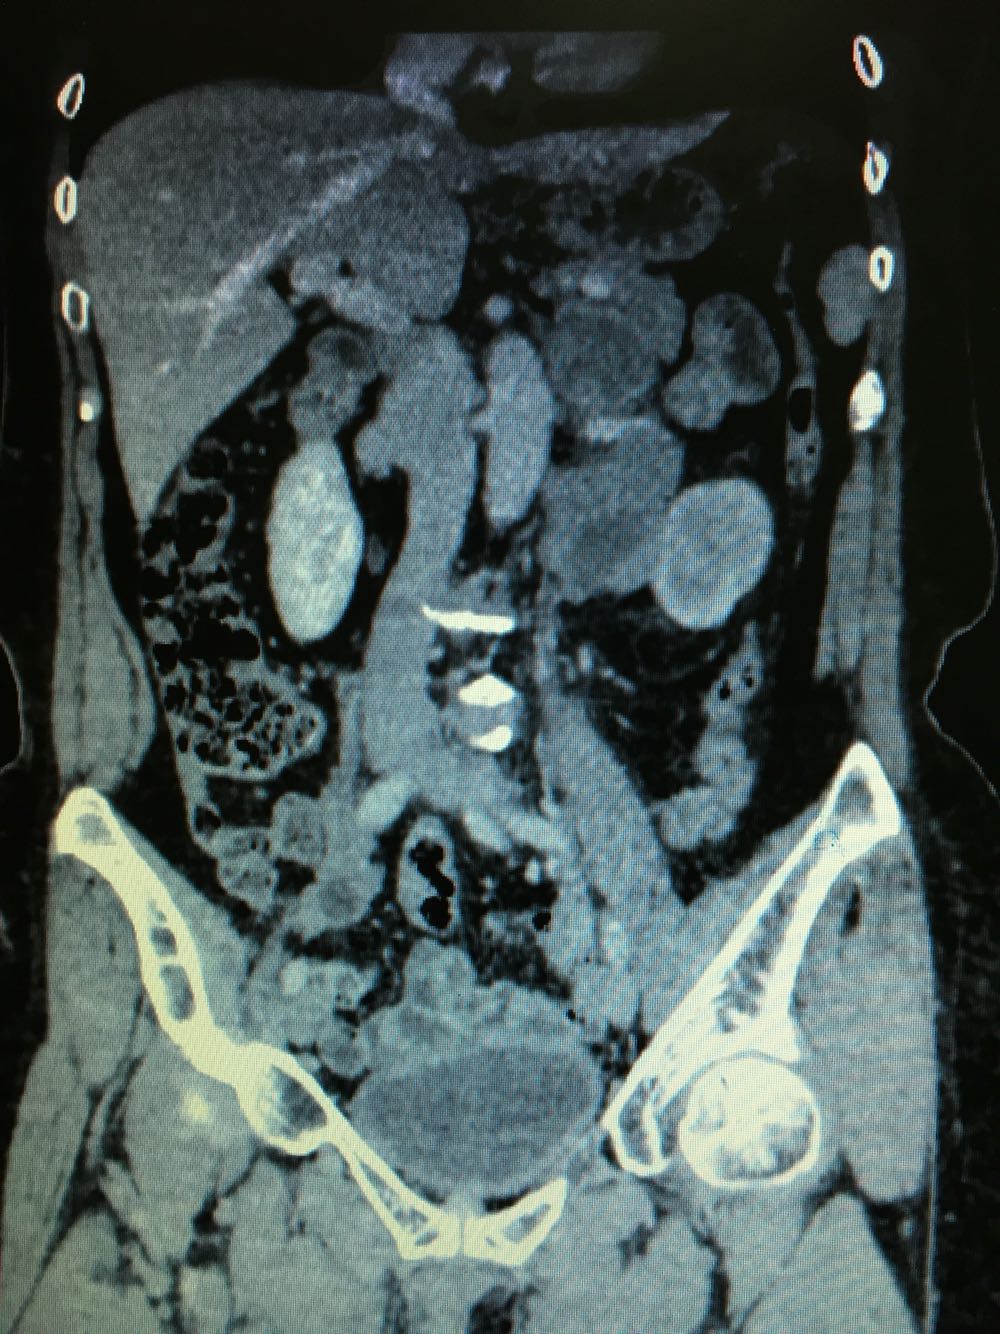

CT提示,左侧肾门处雪人样占位,包裹左肾静脉,左肾积水,与胰腺及左肾关系密切,血常规,肝肾功未见明显异常,GFR左侧27,右侧58。

诊断,左侧腹膜后占位:淋巴瘤?或者淋巴样增生?,侵犯周围器官组织?

探讨下一步治疗方案:该肿瘤位置位于肾门,无法穿刺活检,拟行腹腔镜下探查切除。但,肿瘤与周围组织器官关系密切,术中有可能左肾保不住。但,如果是淋巴瘤的话,化疗效果是很好的。术中快速冰冻,根据病例结果制定方案!